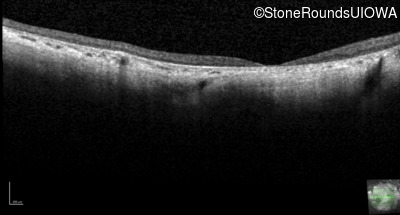

Optical Coherence Tomography - Left - 10/200 -3 sc

Exemplar / OCT Stack

OCT Stack